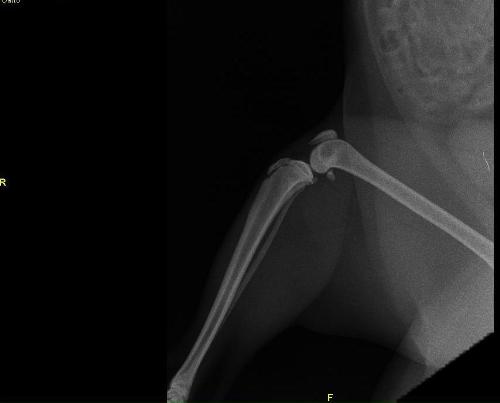

Come steccare una frattura nel gattto. Frattura di femore che si ricompone con mezzo di fissità interno.

Frattura , lussazione falange zampa posteriore sx. Frattura del femore nel gatto. Cure rimedi naturali frattura ossea nel gatto omeopatia inizialmente, a seguito di un trauma il rimedio consigliato è arnica comp della heel. .foto frattura frattura bacino frattura dente frattura mandibola frattura ulna frattura unghia frattura zampa fratture sanitario wustel york shire yorkshire zampa zampa gonfia zampe zampe posteriori zecca zecche zoonosi zoppia zoppie. Soccorso per problemi concomitanti causati dal trauma è la parte più importante del trattamento. Maddy ha il gatto che è stato investito e vuole sapere cosa deve fare, per questo ha chiesto aiuto nella tua lettera ci dici che il micio è stato investito e da allora non poggia più la zampina posteriore. Una lussazione non è visibile come un frattura ma riduce nel gatto la sua capacità di sopportare il suo peso. La frattura del femore è una delle più comuni nel gatto. Il proprietario riferiva che il gatto, rientrato dopo qualche giorno di assenza, probabilmente aveva patito la caduta da un muro di cinta di notevole. Trattamento del metatarso e metacarpo fratture in gatti. Problemi neurologici come deficit propriocettivi; Si chiama borsa primordiale, e ha funzioni precise. A volte, gatti e umani, dobbiamo andare nel nostro giardino segreto. Mao mao è stato trattato alla clinica veterinaria parabiago. Illustrazione dell'icona del fumetto della maschera da portare del gatto fortunato sveglio. Come steccare una frattura nel gattto. Vi siete mai chiesti perché il cane alza la zampa posteriore?